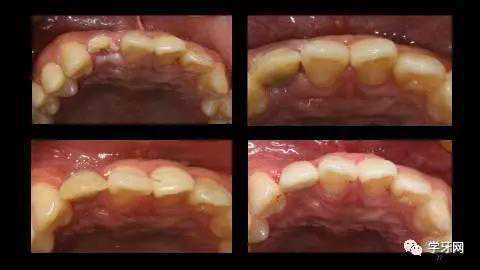

灰色美学分析的中切牙缺失病例。

CBCT调整到中切牙矢状面剖图。测量选择种植体的长度直径。